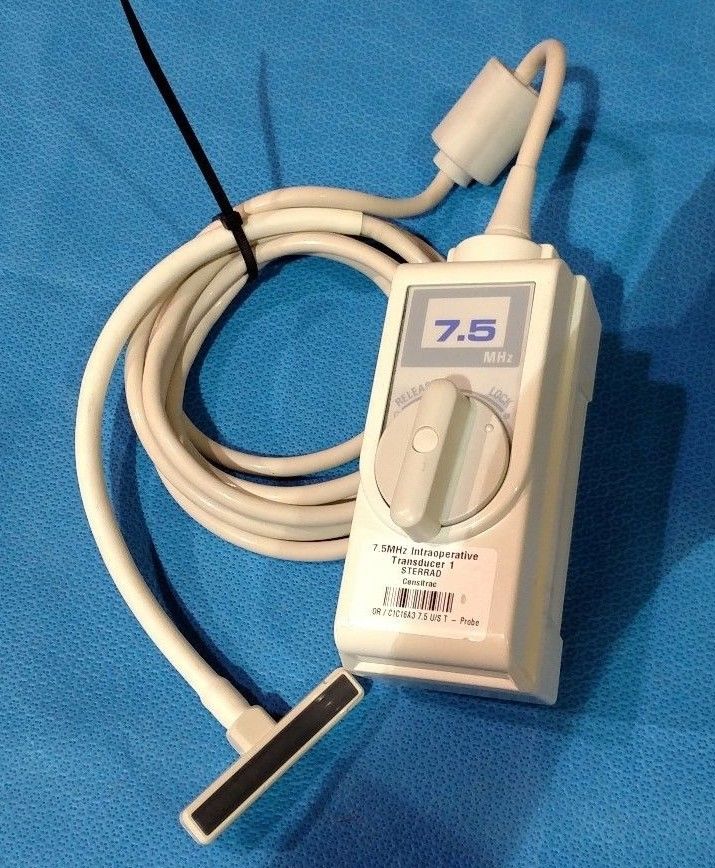

DIAGNOSTIC ULTRASOUND MACHINES FOR SALE

Aloka 7.UST-579T-7.55Mhz Ultrasound Probe

Sale price$ 2,640.38